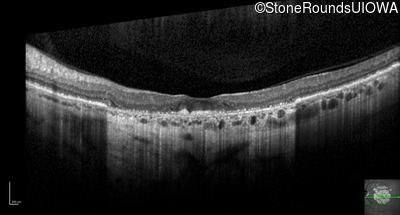

Optical Coherence Tomography - Right - 10/300

Exemplar / OCT Stack